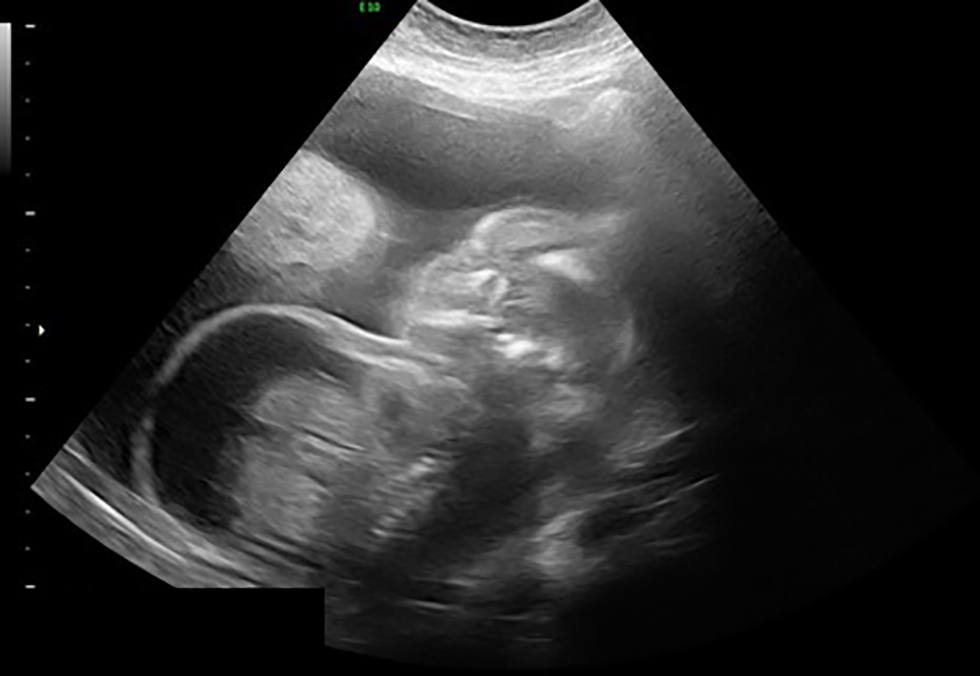

Treatment was continued with intravenous penicillin in the hopes of achieving sufficient levels to treat the fetal infection. After nine days, a repeat detailed ultrasound demonstrated worsening fetal ascites. The fetus was now 20+5 weeks gestation with an abdominal circumference of 282 mm (32+2 weeks size) (Figure 4). The scalp edema and Doppler ultrasound results remained stable. The family was counselled in depth about options, including termination of pregnancy or expectant management with serial ultrasound and fetal magnetic resonance imaging to follow structural neurologic changes. Overall, the prognosis was thought to be poor given the extent of hydrops at early gestation and severity of the changes in the cerebral cortex. Ultimately, the family decided to proceed with termination of pregnancy. Medical induction of labour was carried out with mifepristone followed by vaginal misoprostol. A stillborn hydropic female infant was delivered, indicative of intrapartum demise, at 21+0 weeks gestation and weighing 747 g (greater than 99th centile for gestational age). The family declined an autopsy. The placenta weighed 387 g (over twice the average weight for that gestational age) with pathologic signs of decidual hemorrhage, necrosis and acute inflammation.

Figure 4: Worsening of ascites with abdomen measuring 32 weeks size at 20+5 weeks gestational age

Text description: Figure 4

Ultrasound image, taken at gestational age of 20+5. The fetus is seen in profile, with a markedly distended abdomen with obvious severe ascites. On this day, the fetal abdomen measured approximately 32 weeks size.